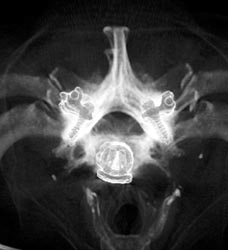

Coalition of Talus and Calcaneus